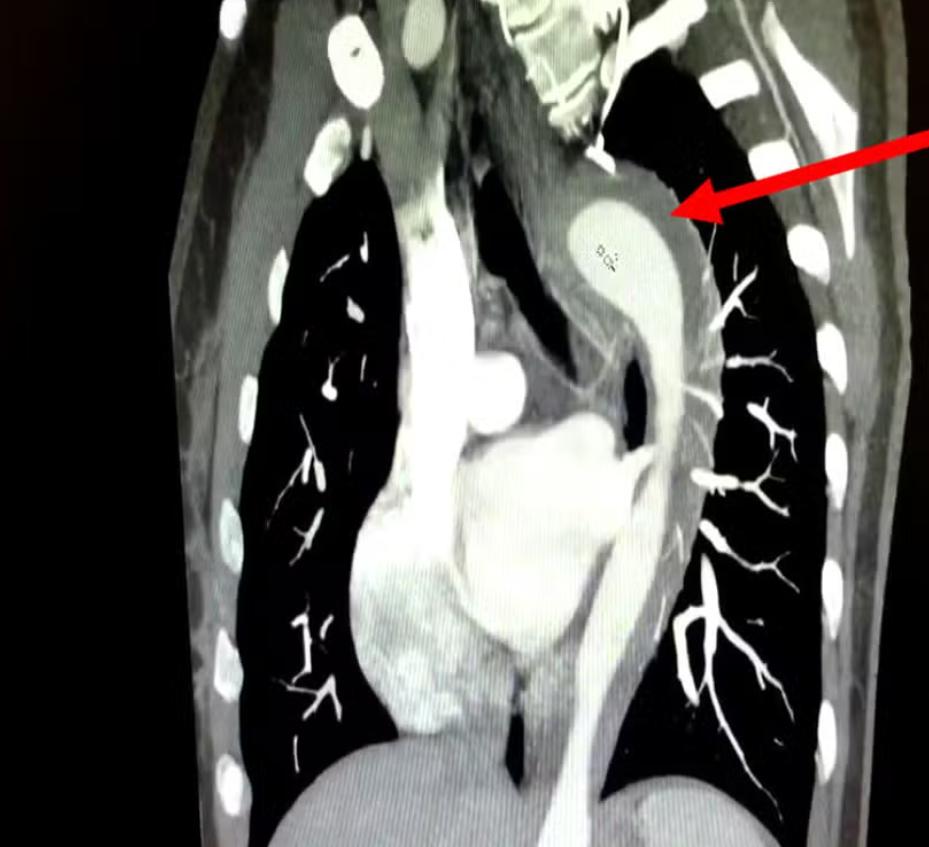

Imagem da aorta rompida após sexo

Legenda: Na emergência, mulher afirmou estar sentindo dores toráxicas após o sexo

Foto: Divulgação/American Journal of Case Reports

Após exames, identificaram um hematoma intramural na aorta, uma grave condição relacionada com o sangramento da parede da aorta. Conforme o g1, o quadro é considerado uma Síndrome Aórtica Aguda (SAA).